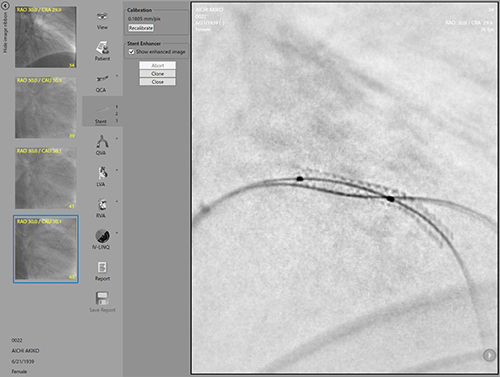

・DICOMビューワ「GoodView」

GoodViewはシンプルなデザインかつ直感的な操作性を追求したDICOMビューワでありながらIVUS像の長軸比較表示,簡易計測機能やファイルフォーマット変換機能など医療現場で求められる多くの声をカタチにした多機能ビューワです。Goodnet専用ビューワとしてだけでなく単体ソフトウェア「GoodViewPRO(Windows対応)」,「GoodView for iPad(iOS対応)」としての提供も行っておりますので是非一度お試しください。

CAAS(Stent Enhancer)